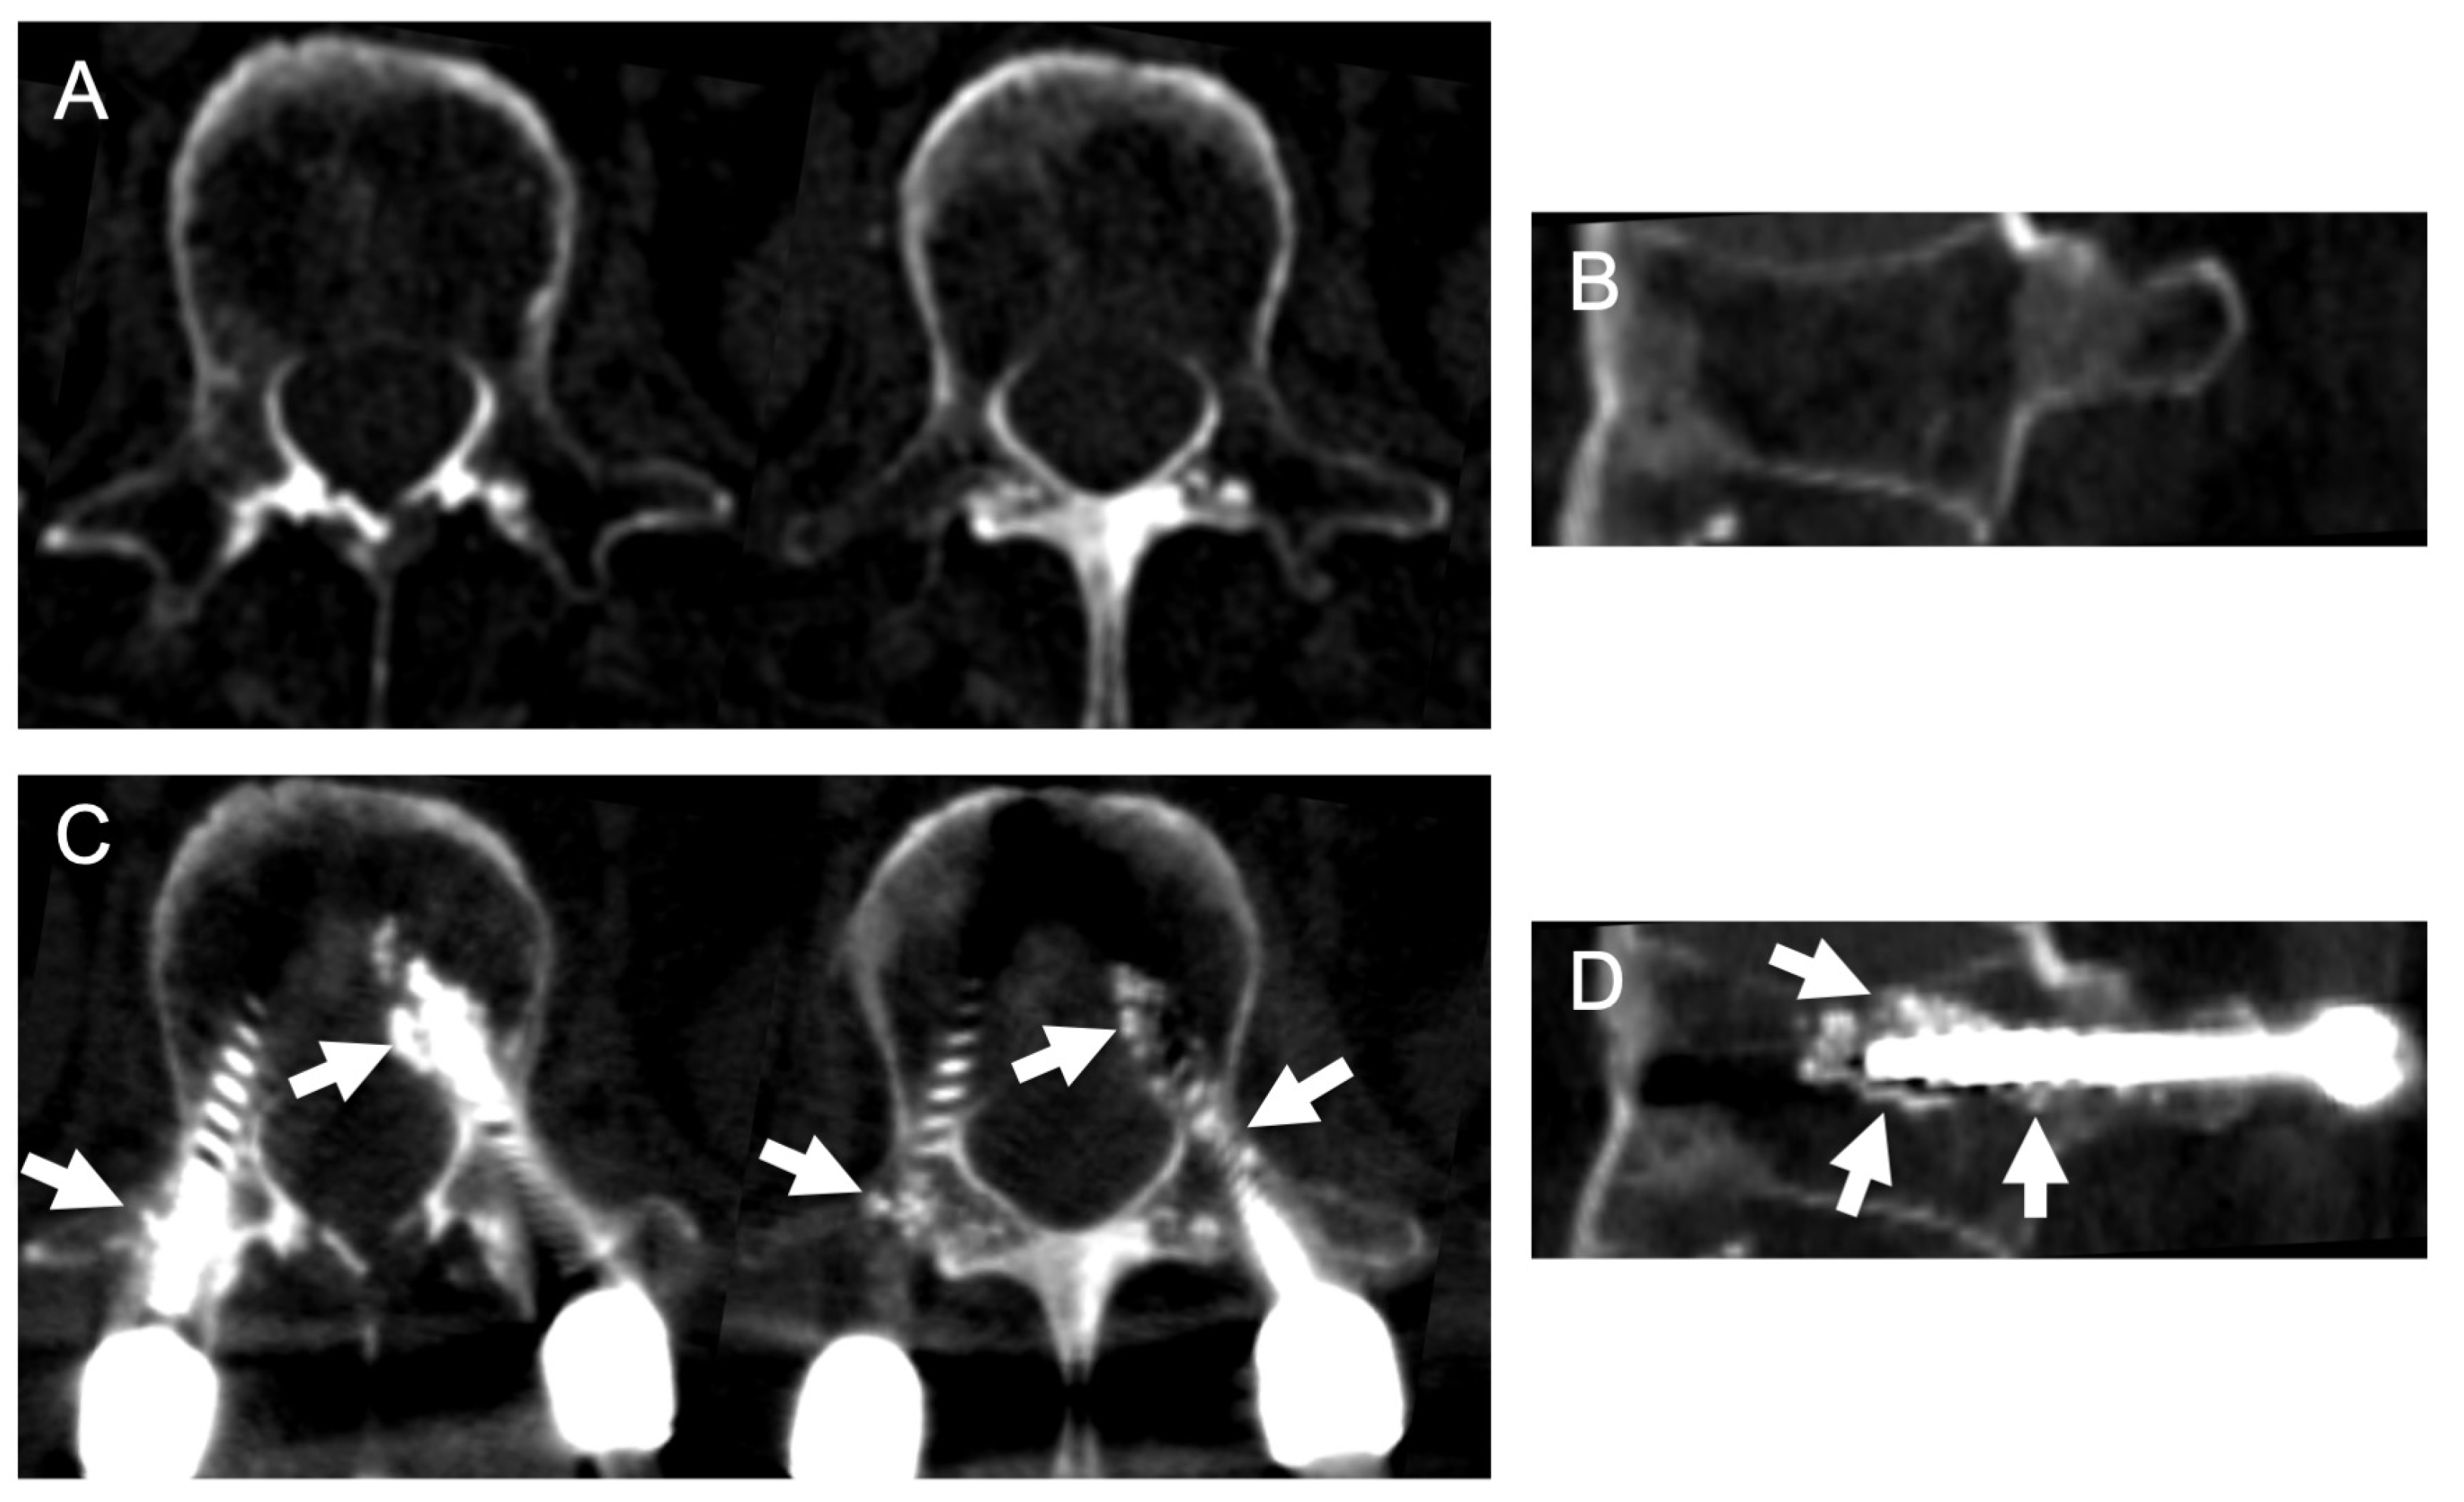

4. Postoperative Stability of PPS Fixation in Osteoporotic Patients

5. Illustrative Case